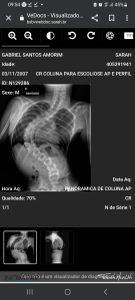

Sou mãe do Gabriel de 15 anos que precisa fazer um tratamento especializado para escoliose de origem  neurológicoca com urgência. Ele tem uma curvatura  de 90° com indicação cirúrgica, porém só  pode fazer a cirurgia  quando passar a fase de crescimento.